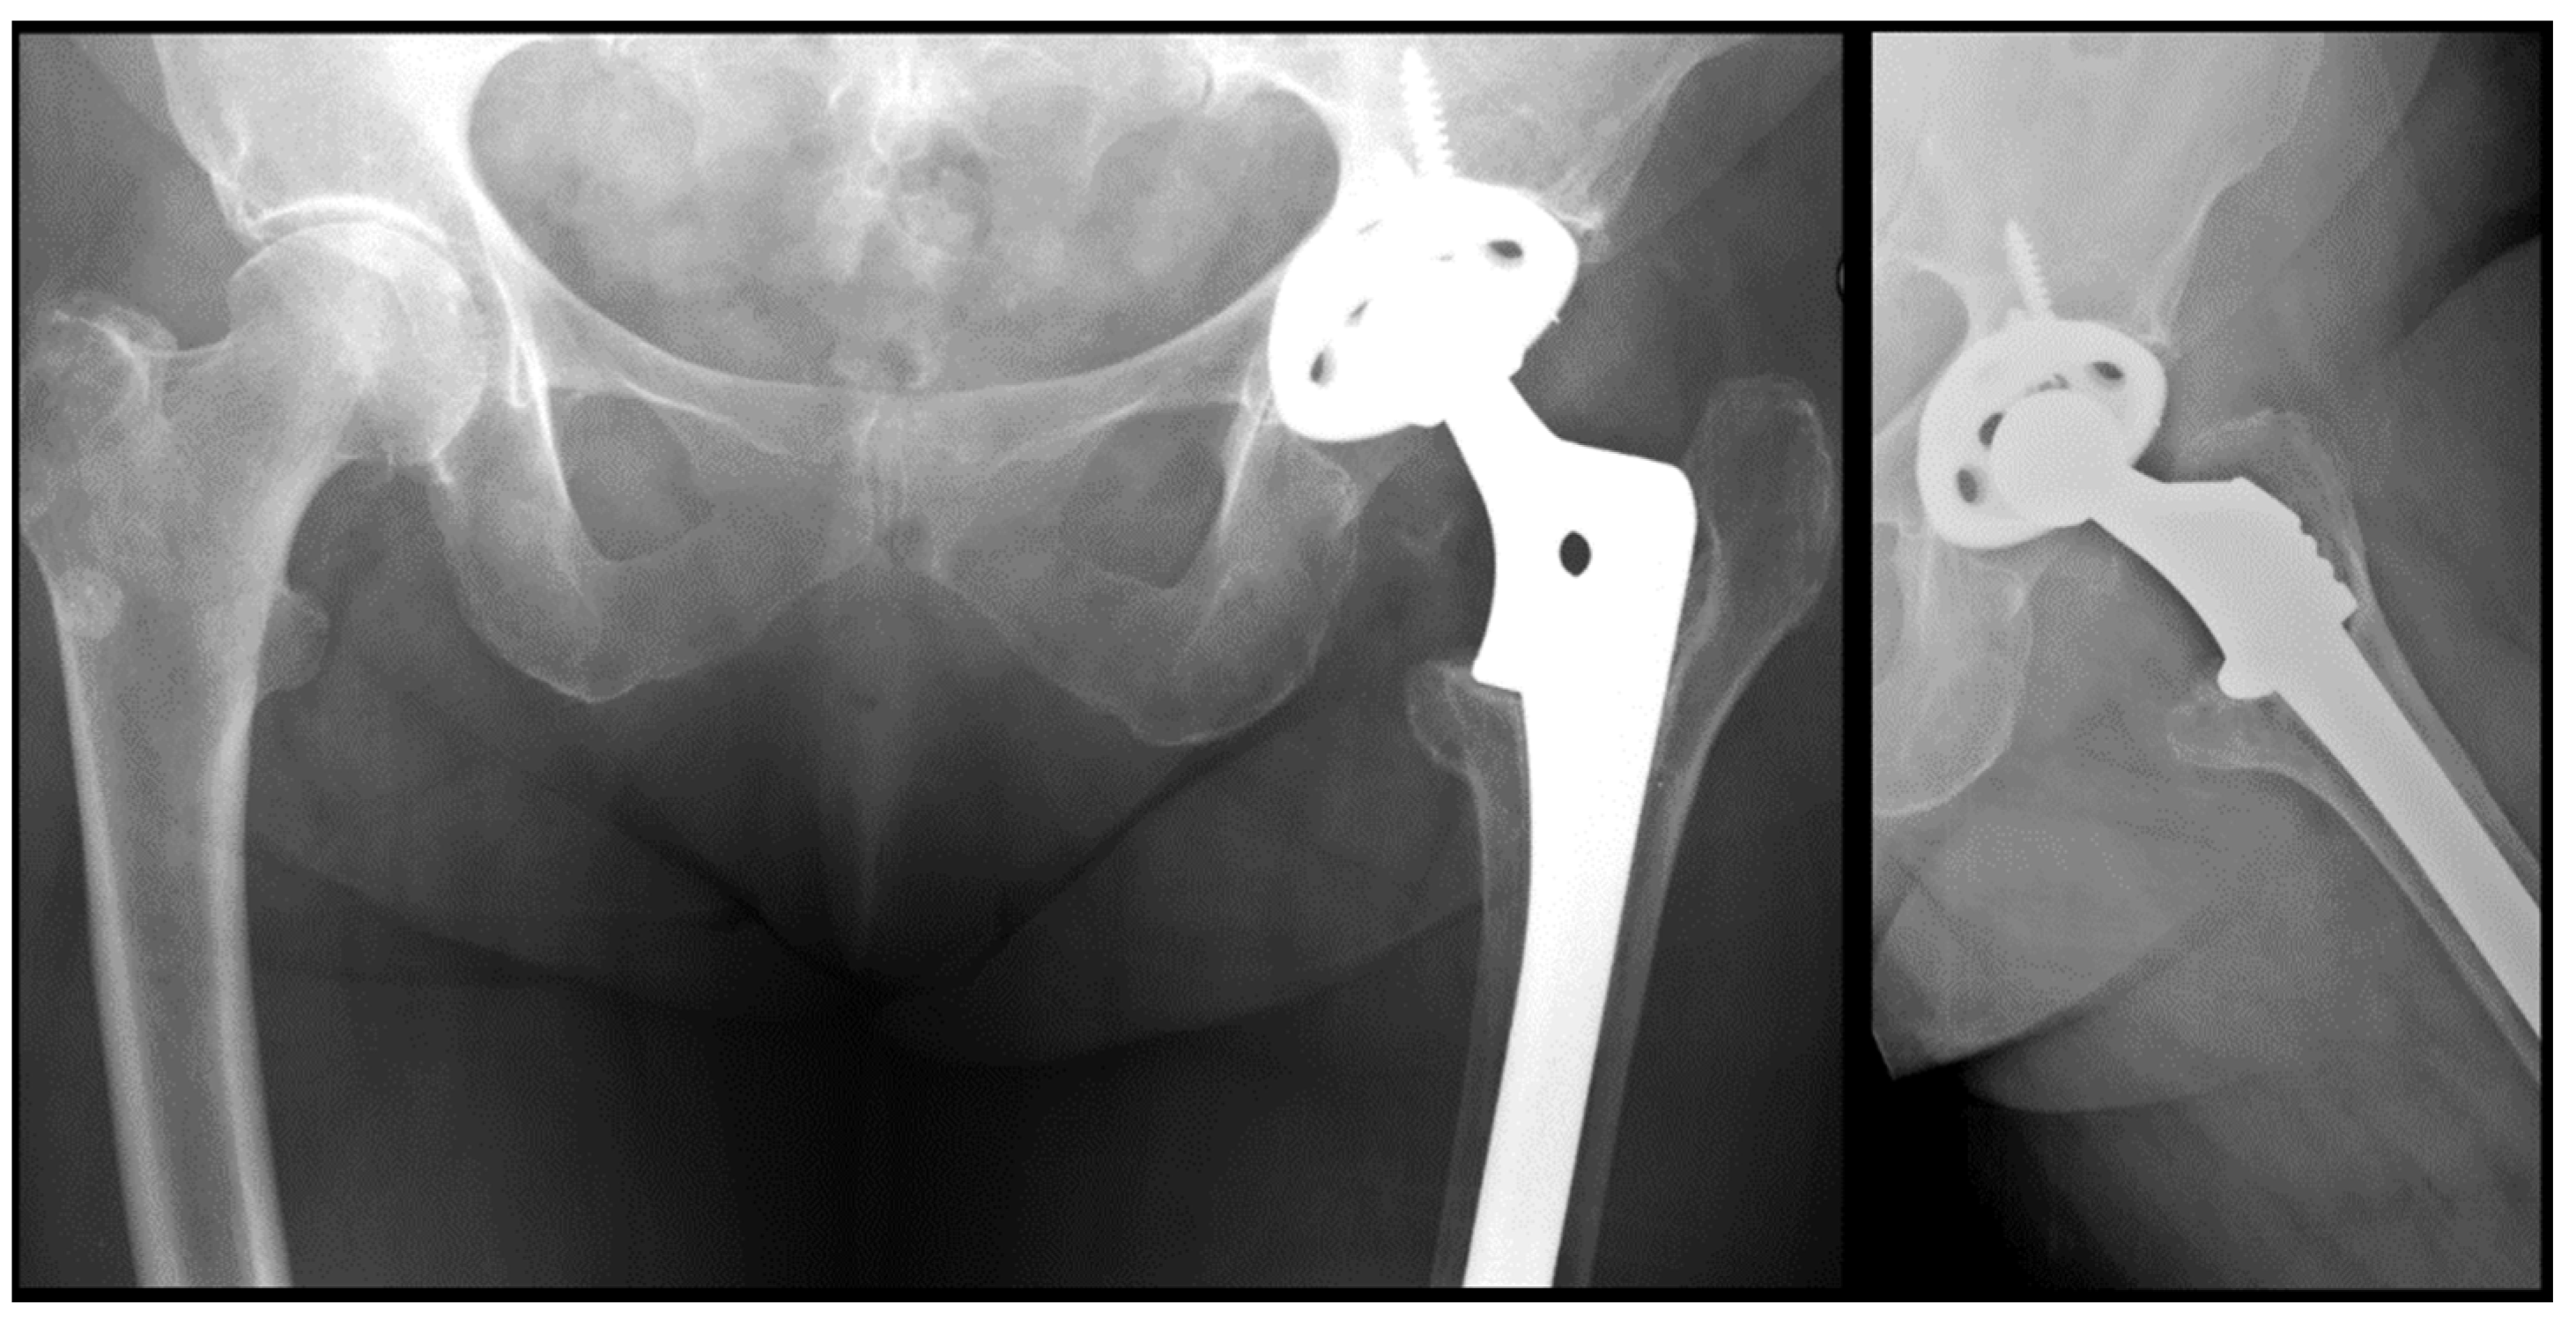

Comparison of Cylindrical and Tapered Stem Designs for Femoral Revision Hip Arthroplasty

2. Materials and Methods

2.2. Radiological Analysis